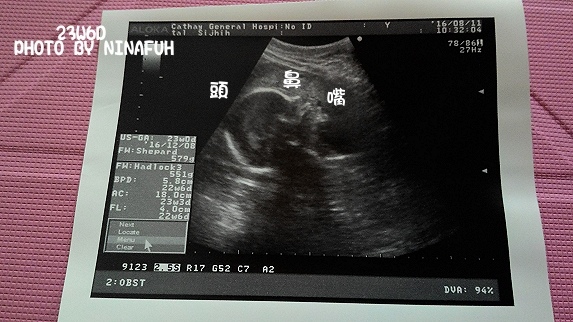

孕期一晃眼就到了快24W~23W6D到醫院進行妊娠糖尿病篩檢~因為現在是空腹先抽一次血~直接喝75G糖水~每間隔一小時抽血~抽兩次~就完成篩檢~多年前懷CoCo瑄只抽一次血~篩檢後沒問題~就不用再第二次篩撿~現在改成連抽三次血~在醫院就要花上三至四小時的時間~中途穿插產檢照超音波~等待時間沒有那麼難熬~ninafuh 發表在 痞客邦 留言(0) 人氣(721)